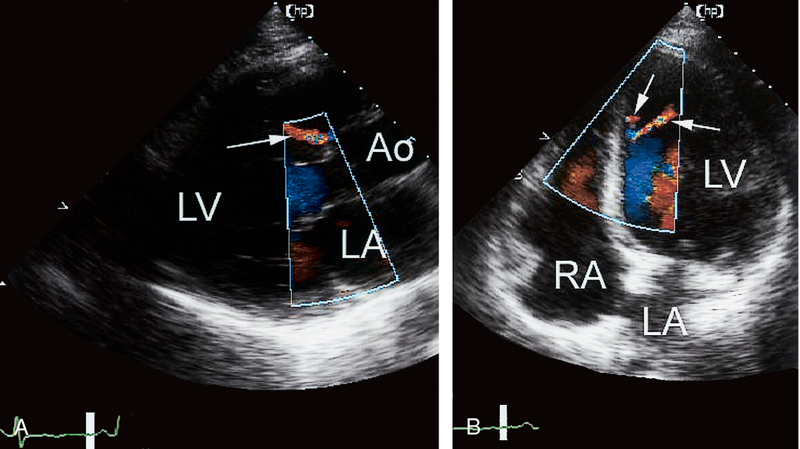

فحوصات تشخيصية لبعض امراض القلب والشرايين التاجية